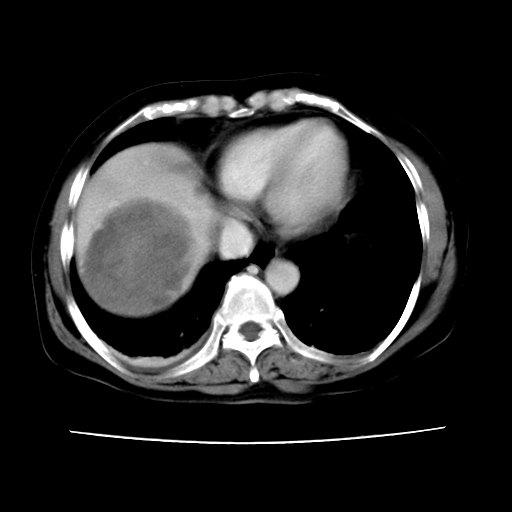

2008-6-10ct平扫

考虑为肝血管瘤破裂出血并肝包膜下血肿;右侧少量胸腔积液。

考虑为肝血管瘤破裂出血并肝包膜下血肿;右侧少量胸腔积液

1)考虑肝癌破裂出血并包膜下血肿;不排除肝腺瘤破裂出血可能。2)肝左叶外侧段囊肿。3)慢性胆囊炎。4)右侧少量胸腔积液。